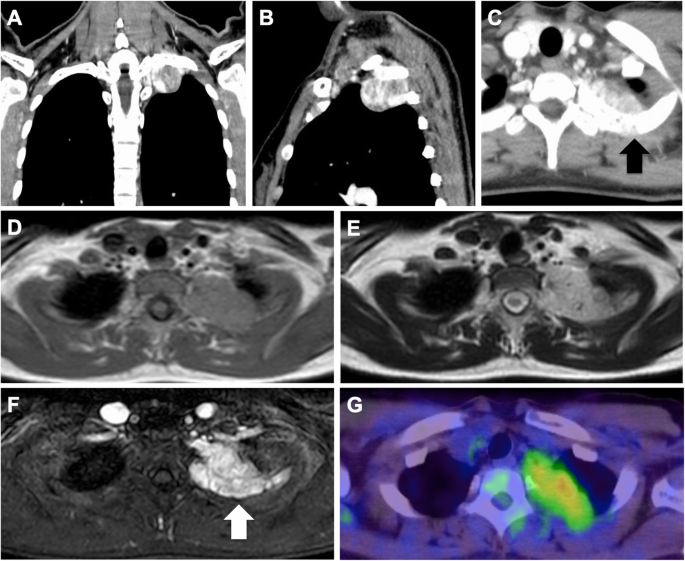

A 31-year-old woman presented with a posterior mediastinal mass on chest computed tomography (CT) scan during a medical check-up two years prior. She had left shoulder pain presentation to our hospital. Contrast-enhanced CT revealed a solitary and non-homogeneous 4-cm mass in the posterior mediastinum invading the left 2nd rib (Fig. 1a, b, c). Magnetic resonance imaging (MRI) revealed that signal inside the mass was equivalent to muscle tissue on the T1-weighted image, and was hyperintense on the T2-weighted image (Fig. 1d, e). Contrast-enhanced MRI showed similar signal changes and contrast effects on the second rib dorsal side in contact with the tumor. Bone infiltration was noted (Fig. 1f). Positron emission tomography/computed tomography scan with F-18 fluorodeoxyglucose suggested that the mass was associated with increased standardized uptake (max = 2.69) (Fig. 1g). All laboratory data were within normal ranges. CT-guided percutaneous fine-needle aspiration biopsy was performed, and she was diagnosed with a neurogenic tumor. We planned tumor resection by RATS combined with chest wall resection.

a Contrast-enhanced computed tomography revealing a solitary nonhomogeneous 4-cm mass in the posterior mediastinum. b, c The mass invaded the left 2nd rib (black arrow). d, e Magnetic resonance imaging (MRI) showing that the signal inside the mass was representative of muscle tissues equivalent to that on the T1-weighted image and hyperintense on the T2-weighted image. f Contrast-enhanced MRI showing similar signal changes and contrast effects on the dorsal side of the second rib in contact with the tumor. Bone infiltration is noted (white arrow). g Positron emission tomography/computed tomography scan with F-18 fluorodeoxyglucose showing standardized uptake values of 2.69